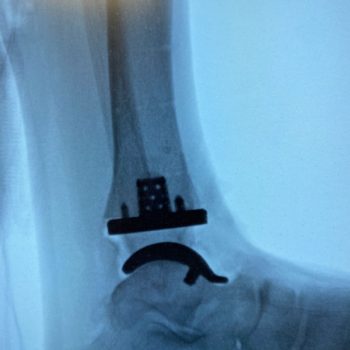

Advita’s Vantage Ankle 3D and 3D+ tibial implants provide surgeons with tibial stem heights from 10 to 30mm and the added benefits of 3D printing. Additive manufacturing creates a surface that mimics the trabecular nature of cancellous bone. Along with the 3D-printed surface, the implants also feature spiked pegs and a tall sharp central cage, with growing diameters, to aid with initial fixation.

“After several years of developing the 3D+ tibial component with the outstanding Advita engineers and other design team surgeons, Jim, Jim [Lachman] and I are pleased how the new tibial components and instrumentation seamlessly melded with the existing talar component options. The additive manufacturing, and the press-fit pegs and augmented central cage afford satisfying initial tibial component stability. Particularly exciting is how the intuitive instrumentation allows for reliable and reproducible insertion of a stemmed tibial component through a routine anterior ankle surgical approach.”